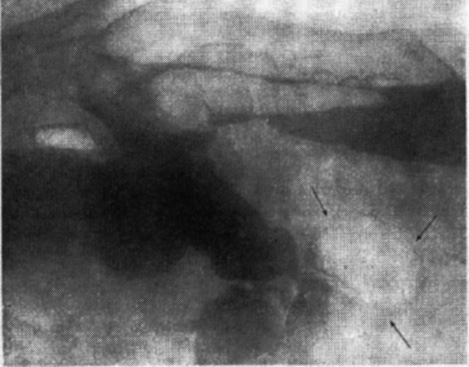

図6. バリウムと空気による大腸二重造影.右側臥位.

【要旨・解説】これ以前の大腸造影法は,ビスマスあるいはバリウム造影剤の注腸による充盈像が基本であったため,小さな病変は造影剤に埋もれてしまい,大きな充盈欠損を来たす病変以外は診断できなかった.本論文では,陽性造影剤である硫酸バリウムと陰性造影剤である空気を併用することにより,より詳細な壁病変を描出する方法を報告している.ここでは単に併用法(kombinierte Methode)と称しているが,いわゆる二重造影である.ただし現在行なわれている二重造影法とは異なり,まず結腸全体を大量の低濃度バリウムで充盈し,いったんこれを排出してからあらためて空気を注入している.空気の注入には二連球を使用し,透視下に観察しながら行なう.

供覧されている写真はいずれも側臥位で撮影されていることもあって,説明文を見ても解釈に苦しむ画質であるが,薄い腸管壁の輪郭やハウストラが明瞭に描出されている点では画期的である(図6).